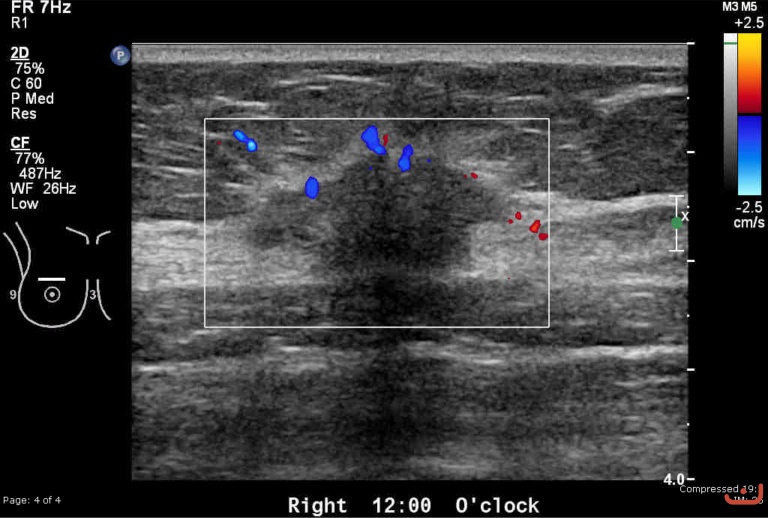

Malignant solid mass

Friday, 22 May 2015